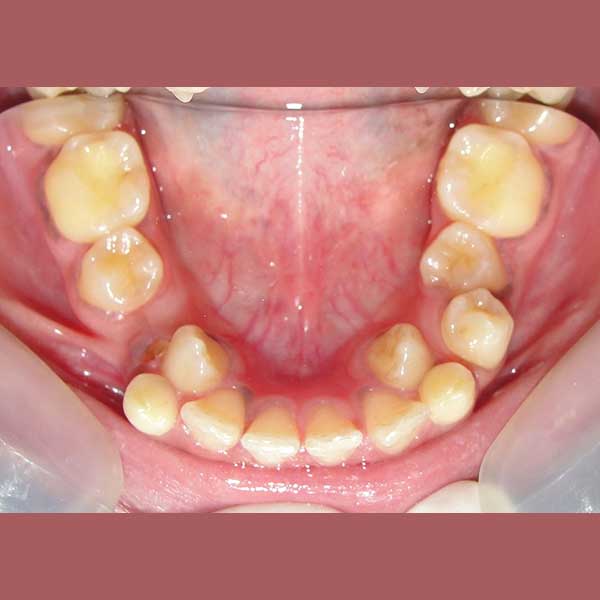

BEFORE

She was complaining about the emergence of her lower canines inward, which causes her big problems in eating and speech, and she wasn’t able to smile comfortably, she even refused To photograph her smile at first.

By examining the case and taking X-rays, I observed the upper canines in her mouth, and an embedded lower premolar was observed too on the left side, I started the treat the case, but because of the old age of this lady, the upper canines and the left lower premolar did not erupt on their own after we extracted the temporary canines, and she had to pull them out by braces. As for the lower jaw; The canines were pulled back in place and the embedded premolar was orthodontically pulled.